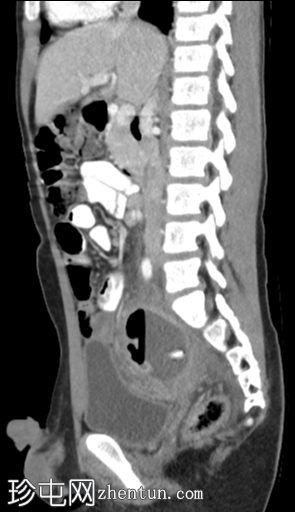

矢状位增强扫描(门静脉期)

2.png

右下腹可见强化且环周增厚的阑尾(轴位、矢状位、冠状位),周围阑尾周围脂肪组织呈条索状改变。阑尾尖端与一个复杂的厚壁积液相通,积液内可见气液平面。积液内可见下垂的钙化灶。积液导致增厚的直肠乙状结肠向左侧移位。

本例为阑尾穿孔继发盆腔脓肿。